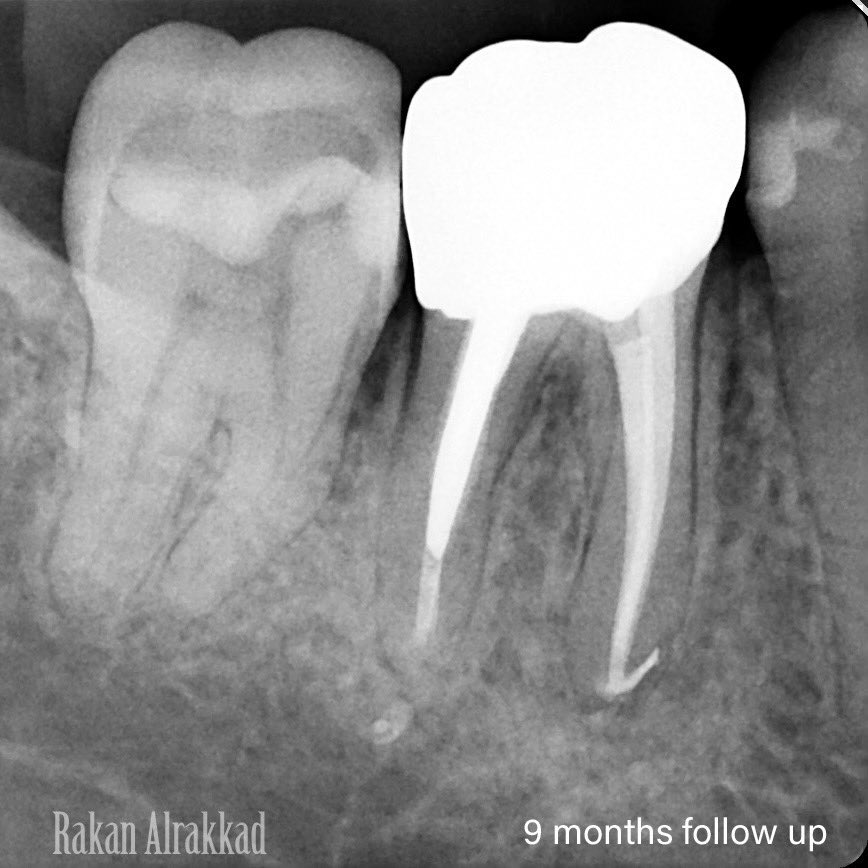

Save the tooth from extraction 🤝🏻 1st : Re-treatment 2nd : Cast post & core 3rd : Surgical crown lengthening Finally: Zirconia crown 👑 Follow up after 9 months and the lesion healed completely

Save the tooth from extraction 🤝🏻

1st : Re-treatment

2nd : Cast post & core

3rd : Surgical crown lengthening

Finally: Zirconia crown 👑

Follow up after 9 months and the lesion healed completely